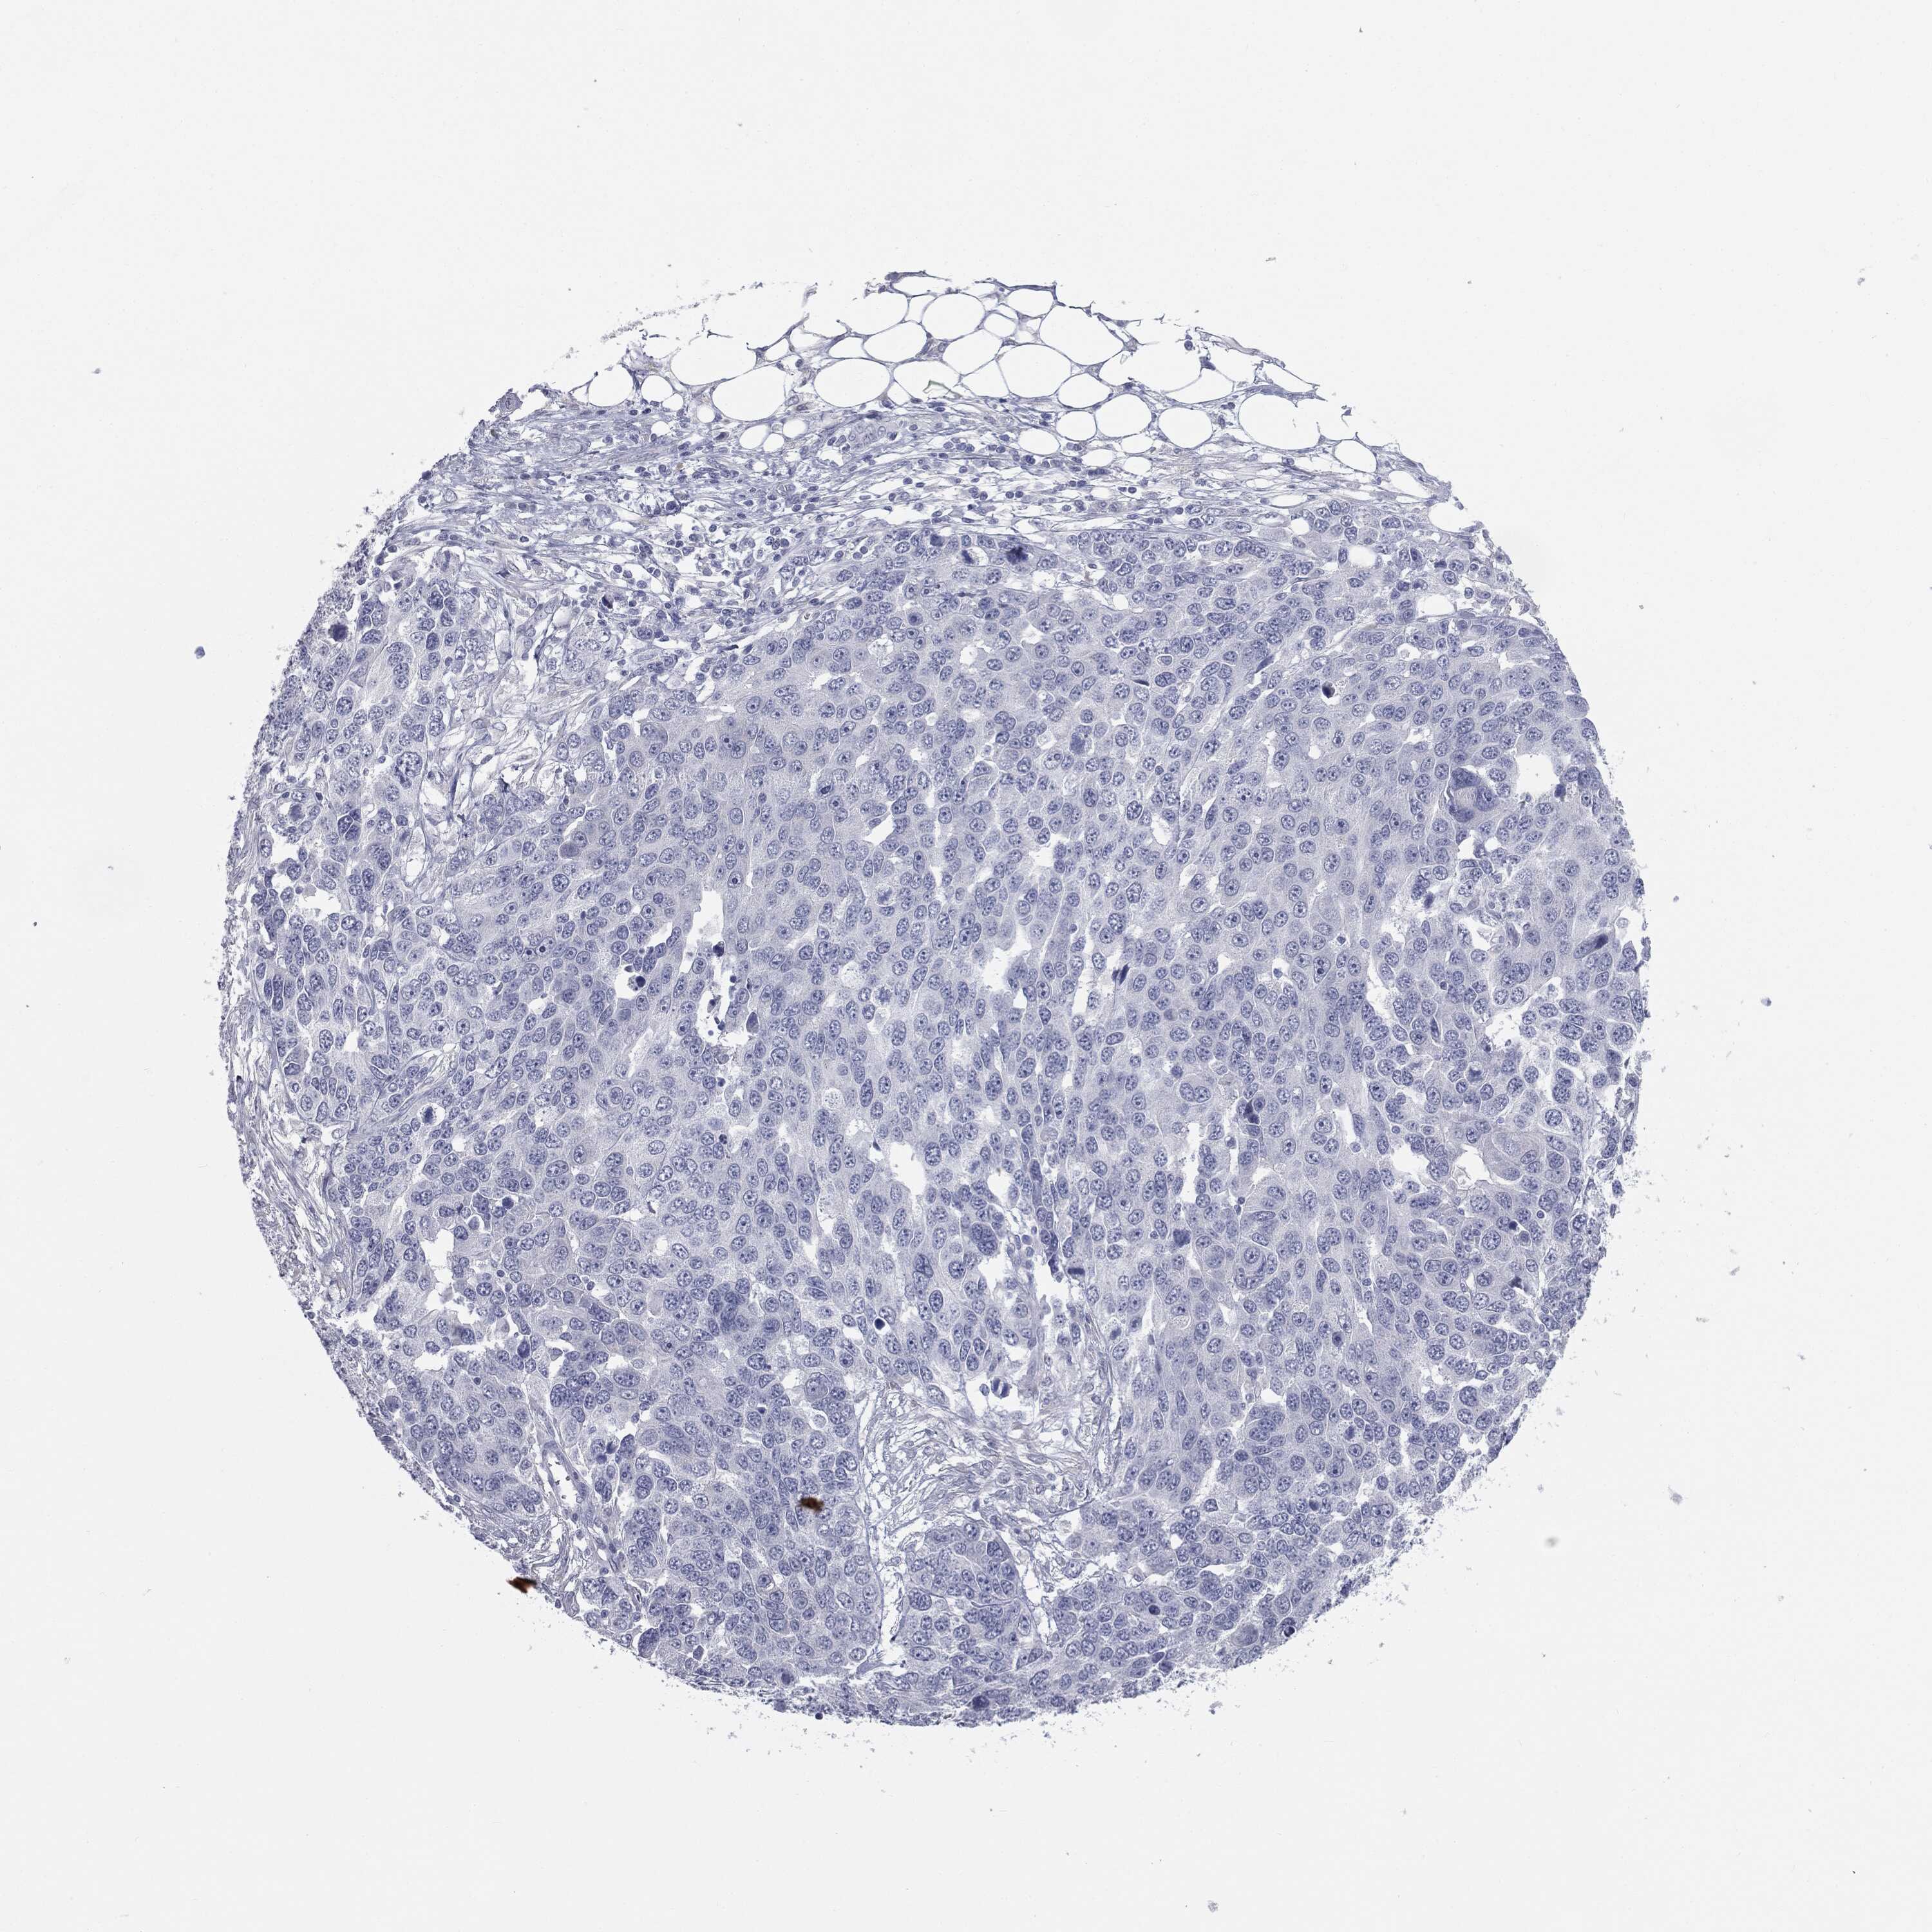

OVARIAN CANCER - Protein expressioni

A mouse-over function shows sample information and annotation data. Click on an image to view it in a full screen mode. Samples can be filtered based on level of antibody staining by selecting one or several of the following categories: high, medium, low and not detected. The assay and annotation is described here.

Note that samples used for immunohistochemistry by the Human Protein Atlas do not correspond to samples in the TCGA dataset.

Antibody stainingi

Antibody staining in the annotated cell types in the current human tissue is reported as not detected, low, medium, or high, based on conventional immunohistochemistry profiling in selected tissues. This score is based on the combination of the staining intensity and fraction of stained cells.

Each image is clickable and will lead to virtual microscopy that enables deeper exploration of all samples and also displays staining intensity scores, fraction scores and subcellular localization as well as patient and tissue information for each sample.

HPA040615

Cystadenocarcinoma, serous, NOS